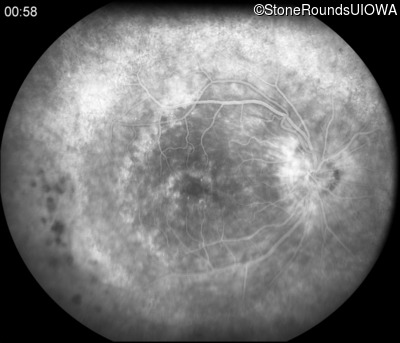

Fluorescein Angiography - Right - 20/50 +2

Exemplar

Fluorescein Angiography - Left - 20/160